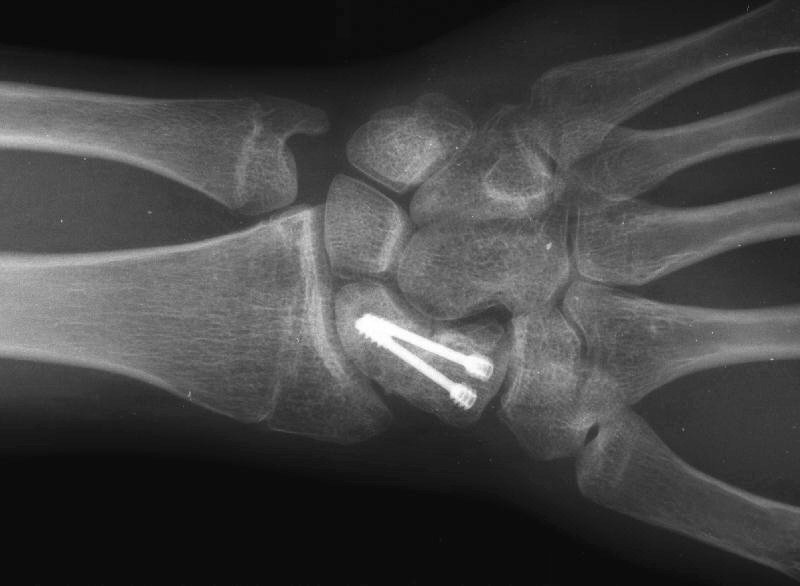

Clinical Example: Revision scaphoid nonunion with hardware removal, bone graft and two Herbert screws

This 19 year old had been treated elsewhere with an accutrac screw for a displaced scaphoid fracture. He was noncompliant with immobilization after surgery, and developed a painful nonunion.

The nonunion was reconstructed by removing the hardware, iliac bone graft and two Herbert screws placed through new paths. Cancellous bone was packed into the old screw hole.